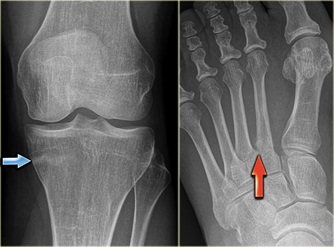

Em geral, o raio X em geral é normal. 80% das fraturas de estresse não são evidentes nas radiografias, salvo nas fases tardias, onde tanto o traço de fraturas, quanto o calo ósseo podem aparecer.

(figura 2): exemplos de ft estresse. Na seta azul, uma fratura de estresse a tíbia e, na vermelha na base do 2.o metatarseano.